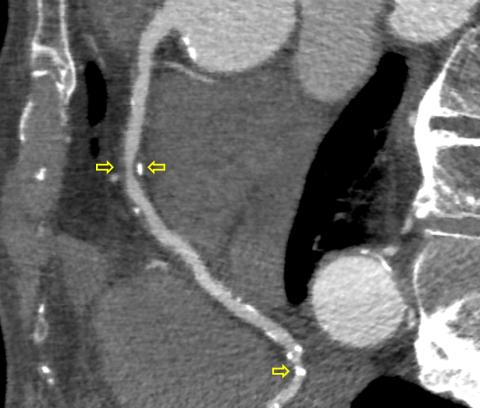

Den primære indikation for hjerte-CT er evaluering af koronare stenoser (mellem de øverste pile) forårsaget af åreforkalkning. Her ses både kalcificerede (hvide, nederste pil), ikkekalcificerede (mørke, venstre øverste pil) og blandede (højre venstre pil) plaques. Denne patient blev henvist direkte til invasiv koronarangiografi og blev revaskulariseret.